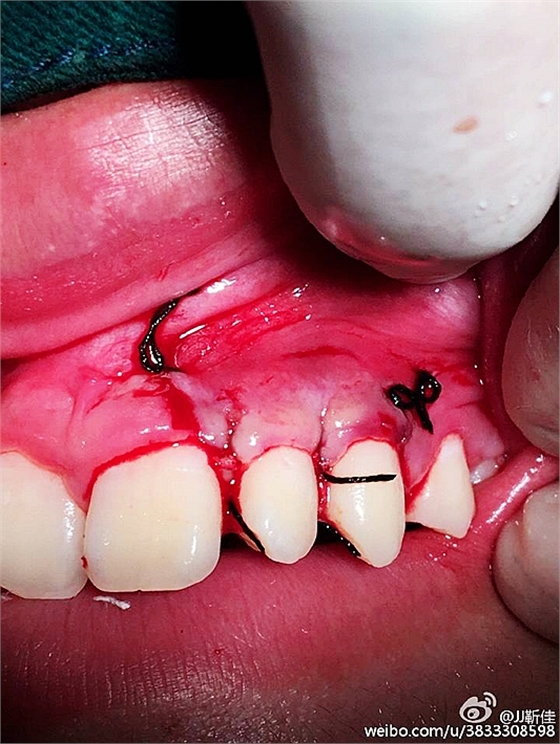

美康口腔王主任手術過程中

局部麻醉。

額外牙拔除

好大的額外牙

植入骨膏

覆蓋骨膜

縫合